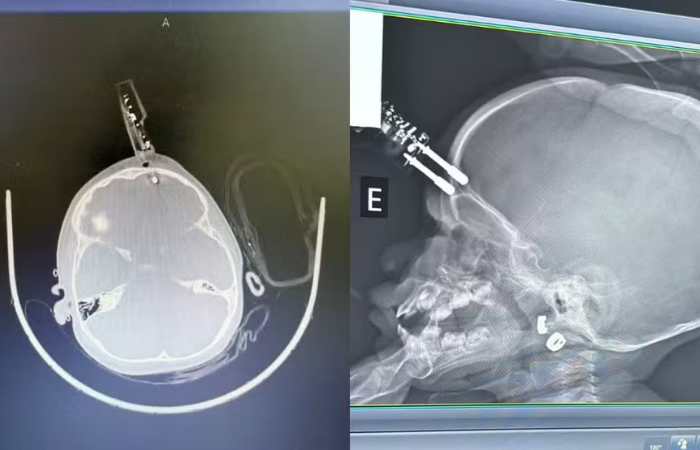

A criança caiu da cama enquanto segurava um carregador de celular. Na queda, os pinos do plugue perfuraram a região frontal de seu crânio, alojando-se na testa, a milímetros da órbita ocular.

O neurocirurgião responsável pelo caso, Dr. Bruno Castro, detalhou que a paciente deu entrada na unidade com o objeto ainda fixado à cabeça.

A equipe médica optou por não remover o carregador imediatamente no pronto-socorro, encaminhando a criança diretamente ao bloco cirúrgico. A medida visava controlar possíveis hemorragias e minimizar danos aos tecidos cerebrais durante a extração.

Segundo o Dr. Castro, a cirurgia envolveu a retirada do corpo estranho, limpeza minuciosa da área para evitar infecções e reconstrução dos tecidos moles e ósseos afetados.